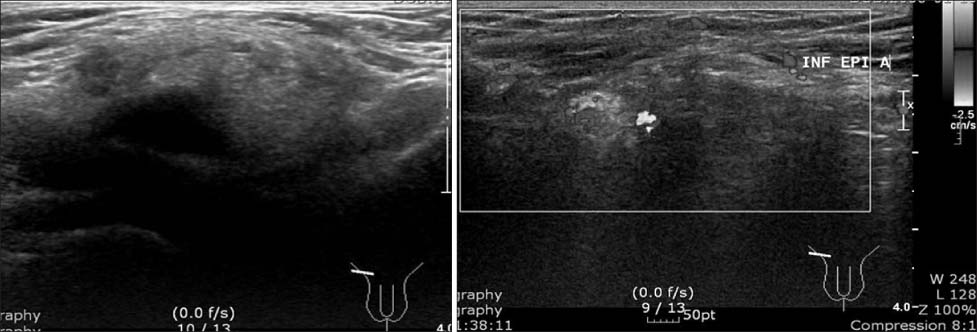

Fig. 1

Ultrasonography showed abnormal echogenic fatty mass in the right inguinal fossa (3×1.3×4.3 cm) with minimal movement during Valsalvar's maneuver.

Fig. 1 Ultrasonography showed abnormal echogenic fatty mass in the right inguinal fossa (3×1.3×4.3 cm) with minimal movement during Valsalvar's maneuver.